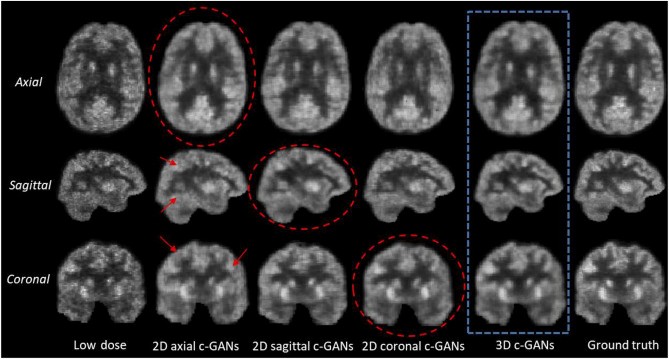

Tests on brain images show 3D model outperforms current methods

Different from other medical imaging techniques that consider an image’s appearance slice by slice, the researchers proposed method is 3D.

“Our technique uses unique machine learning algorithms – known as 3D conditional generative adversarial networks (or 3D c-GANs) – to estimate the high-quality full-dose PET images from low-dose ones,” Dr Zhou said.

Qualitative comparison between estimated results by 2D c-GANs and 3D c-GANs. In the axial and coronal images, the left side of the image is the right side of the brain, and the right side of the image is the left side of the brain. Image courtesy: NeuroImage.